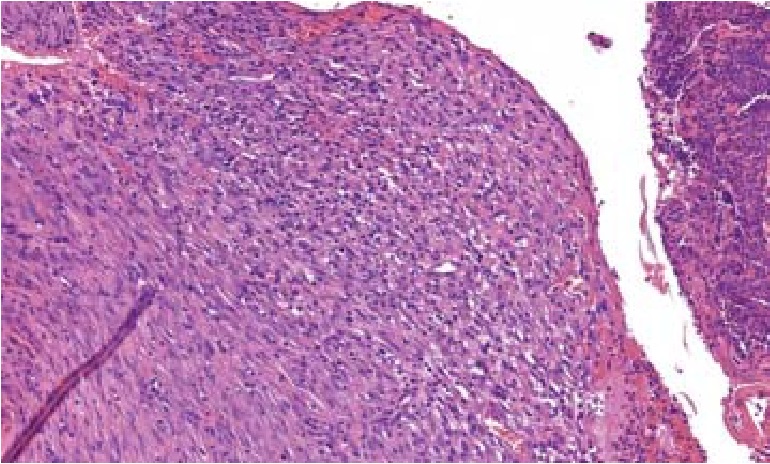

В группе животных, перенесших аппликацию коммерческими раневыми покрытиями на основе гиалуроновой кислоты, на 14-е сутки раневой дефект был покрыт фибринозной пленкой, инфильтрированной нейтрофилами. В подлежащих слоях определялась грануляционная ткань с большим количеством вновь образованных сосудов. Инфильтрация грануляционной ткани нейтрофилами и моноцитами при этом была выражена умеренно (рис. 3).

Рис. 3. Гистологический срез биоптата раны в зоне ожога кожи III степени после ранней некрэктомии, аппликации покрытий на основе гиалуроновой кислоты, 14-е сутки наблюдения. Грануляционная ткань покрыта фибринозной пленкой с умеренной инфильтрацией нейтрофилами и значительным количеством новообразованных сосудов. Окраска гематоксилин-эозином, ув. ×200